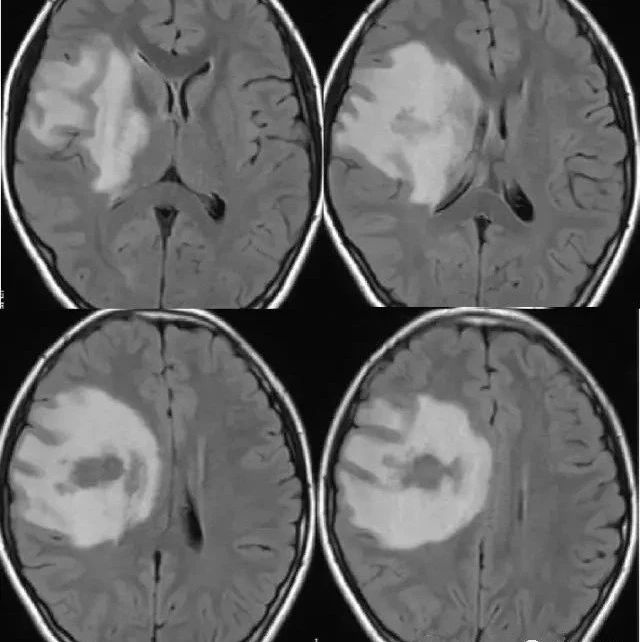

右侧持续头疼半月——颅内真菌性感染 影领学苑 · 公众号 · · 5 年前 · |